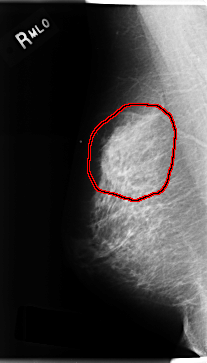

C_0201_1.RIGHT_MLO

RIGHT_MLO LINES 4712 PIXELS_PER_LINE 2688 BITS_PER_PIXEL 12 RESOLUTION 50 OVERLAY

FILE: C_0201_1.RIGHT_MLO.OVERLAY

TOTAL_ABNORMALITIES 1

ABNORMALITY 1

LESION_TYPE MASS SHAPE OVAL MARGINS ILL_DEFINED

ASSESSMENT 4

SUBTLETY 4

PATHOLOGY MALIGNANT

TOTAL_OUTLINES 1

BOUNDARY